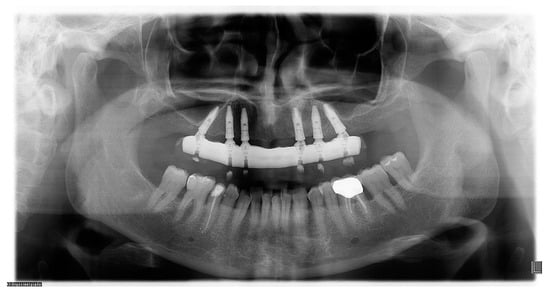

2.7. Radiographic Examination

| Bone Loss | IMPLANTS | |

|---|---|---|

| CIG | DIG | |

| 6 months (mm) | 1.03 ± 0.32 | 0.99 ± 0.48 |

| 12 months (mm) | 1.04 ± 0.56 | 1.08 ± 0.52 |

| 24 months (mm) | 1.07 ± 0.66 | 1.11 ± 0.54 |